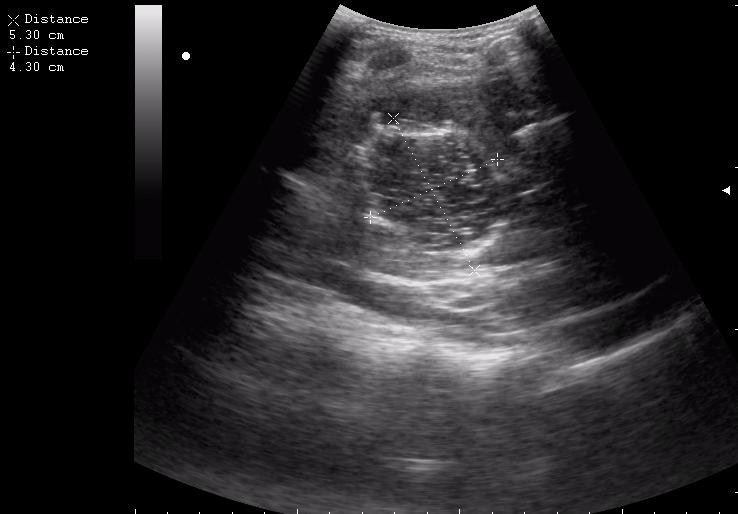

эхинококкоз печени девочка 12 лет.